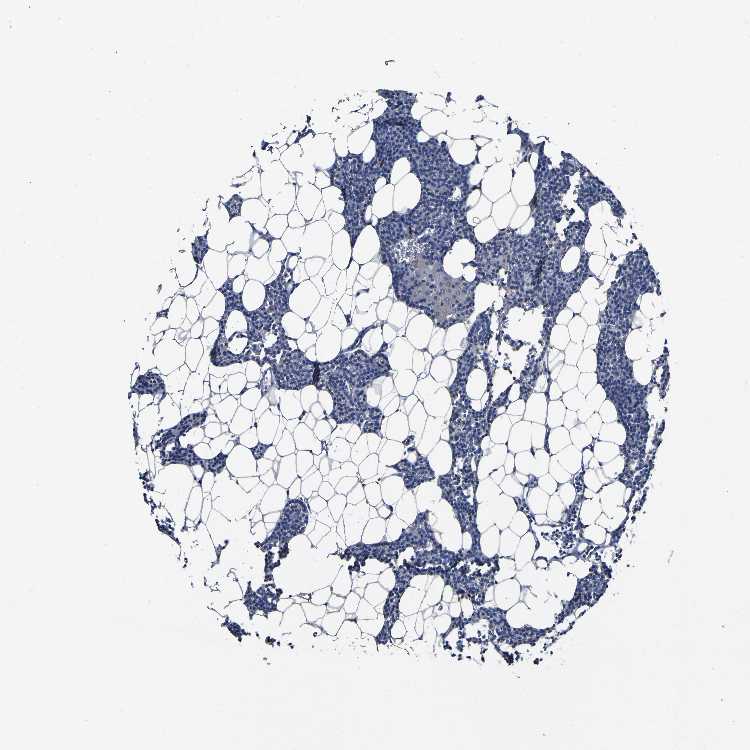

TISSUE PRIMARY DATA PARATHYROID GLAND Show tissue menu

PARATHYROID GLAND - Antibody stainingi

Antibody staining in the annotated cell types in the current human tissue is reported as not detected, low, medium, or high, based on conventional immunohistochemistry profiling in selected tissues. This score is based on the combination of the staining intensity and fraction of stained cells.

Each image is clickable and will lead to virtual microscopy that enables deeper exploration of all samples and also displays staining intensity scores, fraction scores and subcellular localization as well as patient and tissue information for each sample.

Antibody CAB012179

Glandular cells Not detected